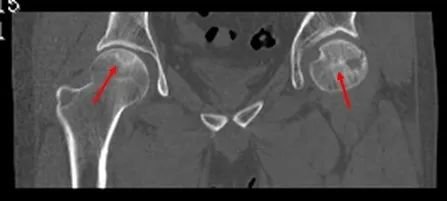

CT检查

CT检查较X线更直观反映坏死的部位、范围,对制定治疗方案具有重要的意义。

股骨头缺血性坏死X线表现